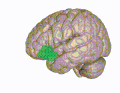

Lateral orbitofrontal cortex -

Medial orbitofrontal cortex, inner slice view -

3D visualization of the orbitofrontal cortex in an average human brain -